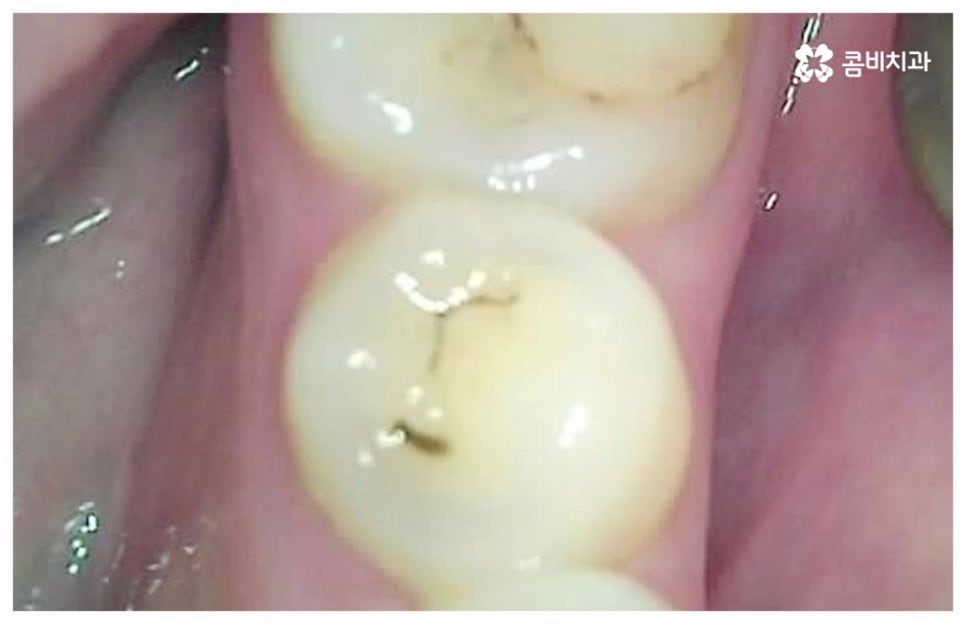

출처 아카이브 열기치통의 원인은 굉장히 다양한데 그 중 가장 대표적인 것으로는 구강 질환과 치아파절을 생각해 볼 수 있을 거예요. 충치나 잇몸병과 같이 구강 내부 상황으로 인해 발생하는 것이 구강 질환이라면 외부에서 충격을 받아 치아가 부러지거나 깨지는 것을 치아파절 이라고 할 수 있는데요. 이렇게 내적 또는 외적인 원인으로 생긴 치아 손상은 자연적으로 낫지 않으며 시간이 지날수록 빠르게 악화되기 때문에 구강 질환이 발생했거나 치아가 파절되었을 때 시기를 늦추지 말고 바로 치과에 내원하셔서 꼼꼼하게 검진을 받고 상황에 적합한 치료를 받으실 필요가 있습니다.

충치나 잇몸 질환은 보통 단계적으로 서서히 발전하기 때문에 환자분들께서 하루 아침에 극심한 통증을 느끼게 되는 경우는 많지 않지만 혹시라도 갑작스럽게 치통이 심할때 혹은 밤에 자려고 누웠는데 더욱 치통이 심할때 는 급성치수염을 의심해 볼 수 있어요. 급성치수염은 언급했던 충치나 외상성 치아 파절로 인해 치아 가장 안 쪽에 있는 치수 부분까지 세균이 침투하여 염증이 발생하는 것을 의미하는데, 이 때 감염된 혈관이 부어오르면서 단단한 치아 외벽에 둘러쌓인 치아 내부 압력이 올라가 작은 움직임에도 극심한 통증을 느끼게 되는 거예요.